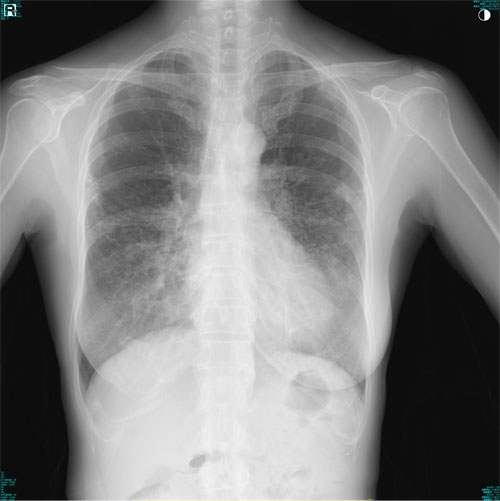

肺X線画像

- 2023.05.11 要観察と診断された画像(国立系病院)